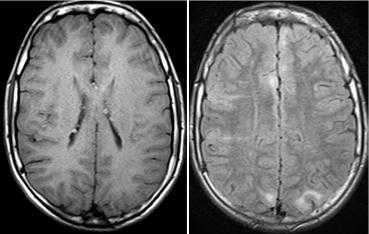

Субэпиндемальные узлы и корковые туберсы на МРТ

При подозрении на эту болезнь обязательно следует проводить МРТ головного мозга. При этом в головном мозге выявляются характерные МРТ-признаки туберозного склероза: корковые и подкорковые узлы (туберсы), субэпендимальные узелки (гамартомы), а также различные изменения белого вещества - очаговые и кистозные.

МРТ головного мозга при туберозном склерозе. Участки изменения МР-сигнала неправильной формы в коре и подкорковом белом веществе — так называемые корковые туберсы.